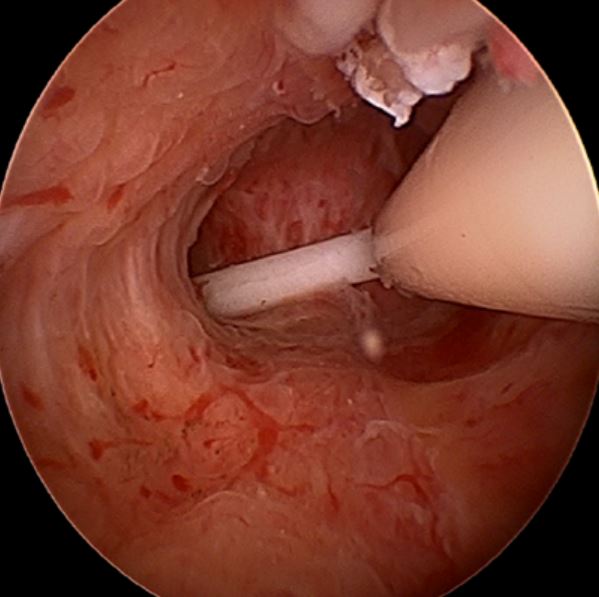

0 comments on “Hysteroscopy Pictures”